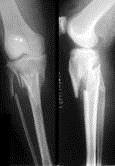

病历摘要: 患者×××,男性,65岁,因车祸致伤左小腿后肿胀、活动受限、疼痛2小时。查体:左小腿上端肿胀,触痛(+),触及在骨擦音,左足伸足母、伸趾功能正...

问题 病历摘要: 患者×××,男性,65岁,因车祸致伤左小腿后肿胀、活动受限、疼痛2小时。查体:左小腿上端肿胀,触痛(+),触及在骨擦音,左足伸足母、伸趾功能正常,足背动脉搏动正常。 胫骨平台骨折的并发症有哪些?

选项 A、膝内外翻畸形 B、小腿筋膜间隙综合征 C、骨折不愈合 D、骨折延迟愈合 E、膝关节功能障碍 F、胫神经损伤 G、感染 H、胫前动脉、胫后动脉损伤 I、腓深神经损伤 J、骨折畸形愈合